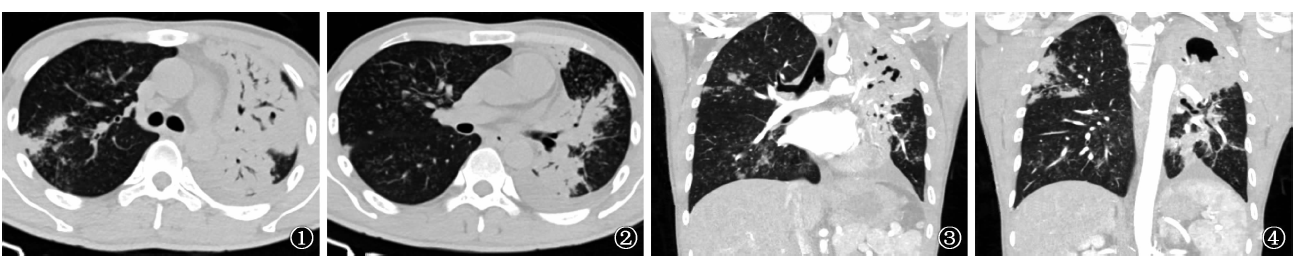

图1~4

图1

、2为胸部CT横断面扫描,显示左肺大片实变影,其内可见支气管充气征象、支气管扩张及空洞,右上叶后段胸膜下可见斑片影,双肺各叶多发腺泡结点样播散灶。左侧胸腔见少许积液。

图3

、4为胸部CT冠状位重建,显示左肺大片实变影,其内可见支气管充气征象、支气管扩张及空洞,右上叶后段胸膜下可见斑片影,双肺各叶多发腺泡结点样播散灶